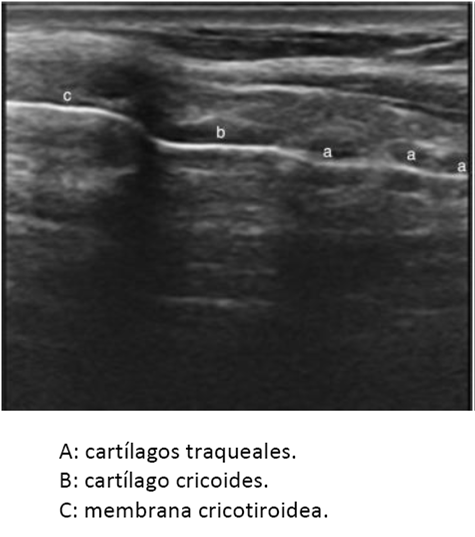

El uso de ultrasonido es de gran utilidad para poder identificar la membrana cricotiroidea, sobre todo en personas obesas q tienen abundante grasa en el cuello, a través de un corte longitudinal a lo largo de la laringe, se observa un estructura hipoecoica que se encuentra entre el cartílago tiroides y el cartílago cricoides. (Figura 2). A este nivel es posible identificar la membrana, empleando modo dopper color, vasos sanguíneos presentes sobre las estructuras laríngeas y traqueales, de tal manera que si se piensa realizar una punción translaríngea a ese nivel, se puede escoger el sitio en donde no se tenga riesgo de punción vascular (10).